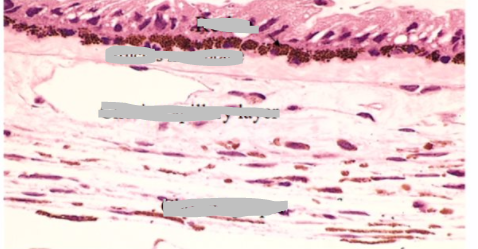

describe the choroid

A

• function:

• absorption of stray light

• blood retinal barrier

• choroid proper:

• presence of large blood vessels

• melanocytes

• choroid capillary layer

• fenestrated capillaries

• Bruch’s membrane:

• between choroid and retinal pigment layer

• component of blood retinal barrier